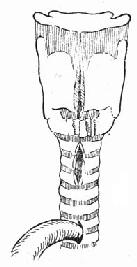

(1)急性声门上损伤:声门上损伤包括甲状软骨板上半部骨折和会厌损伤(图96-1)。有急性喉阻塞者首先行常规气管切开术,然后行前连合直接喉镜检查,注意喉水肿和喉及下咽粘膜裂伤的情况。手术包括缝合粘膜裂口并切除会厌及会厌谿之血肿组织,颈前在舌骨水平做横切口,剪断舌骨后,给行切开甲舌膜进入咽腔(图96-2)。切除会厌,会厌根部血肿组织及双侧假声带(图96-3)。用丝线缝合喉粘膜,尽量对合复位骨折的甲状软骨板,并用丝线缝合甲状软骨外板软骨膜,再缝合甲舌膜(图96-4)。逐层缝合切口。术后48h经鼻咽置入下咽部一条吸引引流管,持续引流。待喉部手术后反应消退,可试行堵管,呼吸道通畅即可拔除气管套管。

图96-1 声门上损伤

图96-2 声门上损伤手术方法 剪断舌骨,纵行切开甲舌膜。